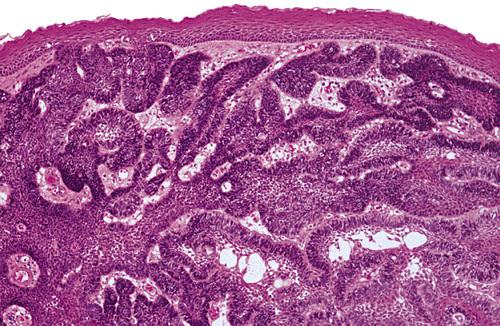

Histopathologic Features

- lined by squamous epithelium of varying thickness

- uneven hobnail and sometimes papillary surface

- mucin-producing goblet cells in the surface layer

- glandular, ductlike spaces within the epithelial lining

- mucicarmine-positive fluid within spaces

The cyst is lined by stratified squamous epithelium that exhibits surface columnar cells with cilia. Numerous microcysts containing mucinous material are present.

glandular odontogenic cyst